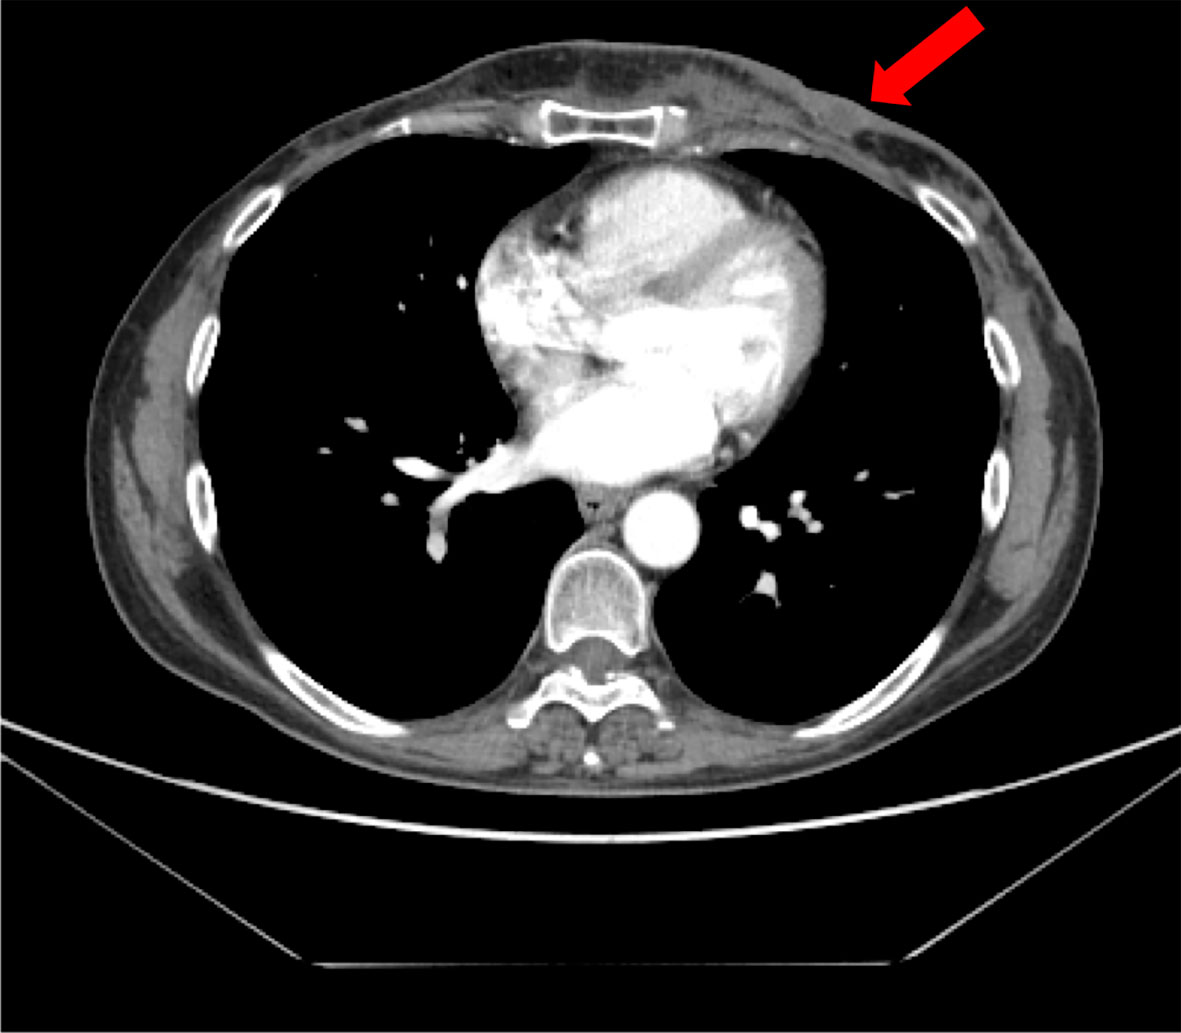

FIGURE 4

Figure 4 (A) CT scan images of left chest wall disease progression at enrolment in the IMpassion131 trial. (B) CT scan images at enrolment in CLAG525B2101 trials. (C) Complete response after 6 months of treatment with olaparib; no contrast enhancement at PET-CT scan.

In February 2020, as a patient with a germline BRCA mutation who had received no more than two previous chemotherapy regimens for metastatic disease, she was eligible for olaparib (300 mg twice daily) therapy (Figure 4B). Treatment was well tolerated apart from G2 anemia, which imposed a dose reduction—the olaparib dose after 7 months was 100 mg plus 150-mg tablets twice daily. Other reported AEs were nausea, vomiting, and diarrhea (all G1). There was no evidence of increased uptake on PET/CT scan (Figure 4C). Treatment with olaparib produced a complete response after 6 months, and at the time of writing, the patient had a PFS of 40 months. It should be, moreover, emphasized how grateful the patient was to be able to receive an effective therapy that did not negatively affect her QoL. Indeed, she had been aware of the advanced stage of disease since she was 45, and that the PFS with the first line of treatment was only 5 months. The complete disease response achieved with a long-lasting and overall well-tolerated oral treatment also increases adherence to the therapy itself, enhancing its efficacy.